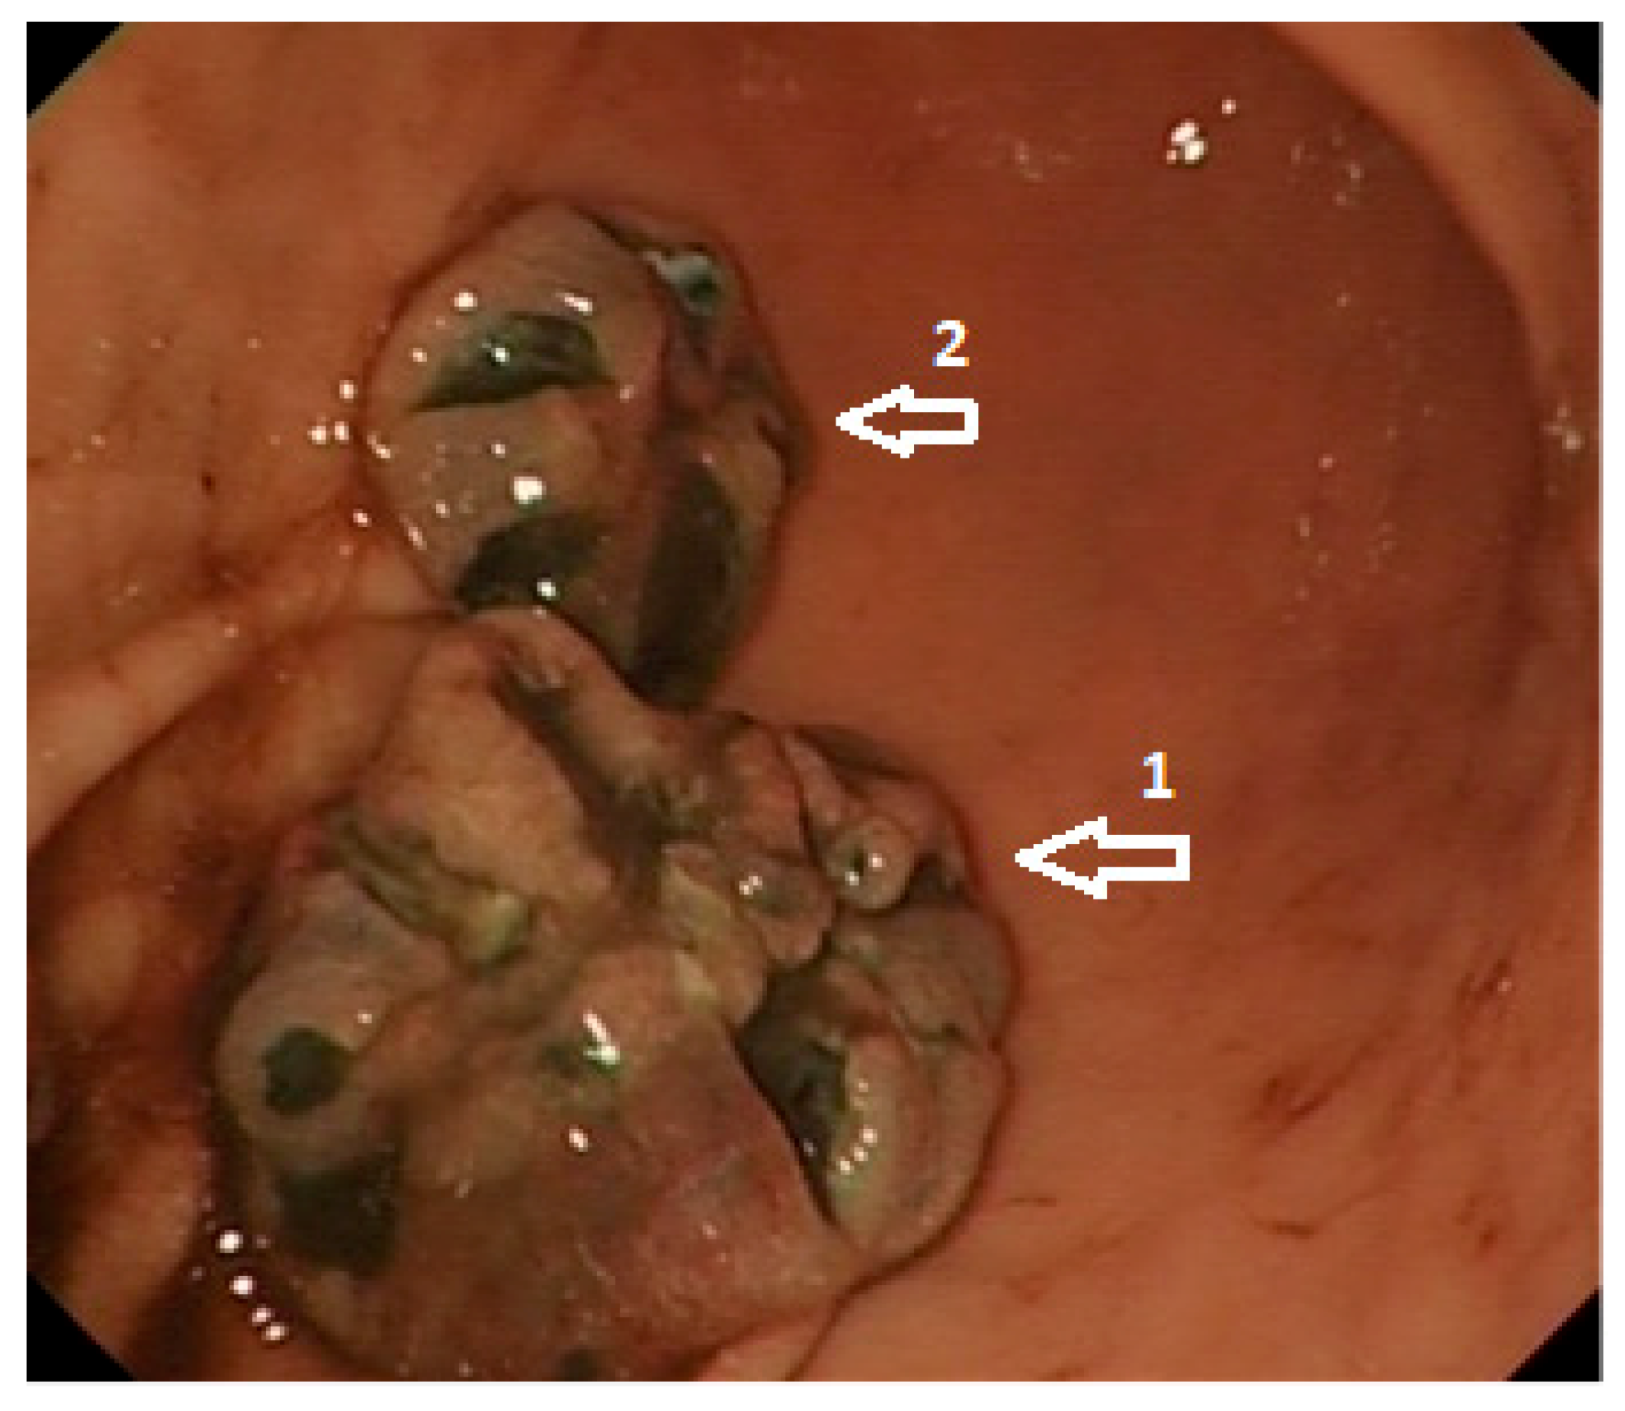

1.4. Diagnosis

1.6.1. Endoscopy